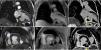

From the time of admission, the patient presented pathological Q waves and negative T waves in III and aVF on the electrocardiogram (ECG), suggesting inferior myocardial scarring. Transthoracic echocardiography showed deformation of the inferior wall, expanding in systole, and apparent reduction in wall thickness, together with a small pericardial effusion, suggesting a pseudoaneurysm rather than a true aneurysm (Figure 1 and Video 1).

Transthoracic echocardiograms suggestive of pseudoaneurysm of the inferior wall (arrow). (A and B) Apical 2-chamber view shows aneurysm of the inferior wall with reduced wall thickness and color Doppler suggesting flow between the ventricle and the aneurysm; transverse section, parasternal short-axis view in basal (C) and subcostal (D) planes. Small pericardial effusion (*).